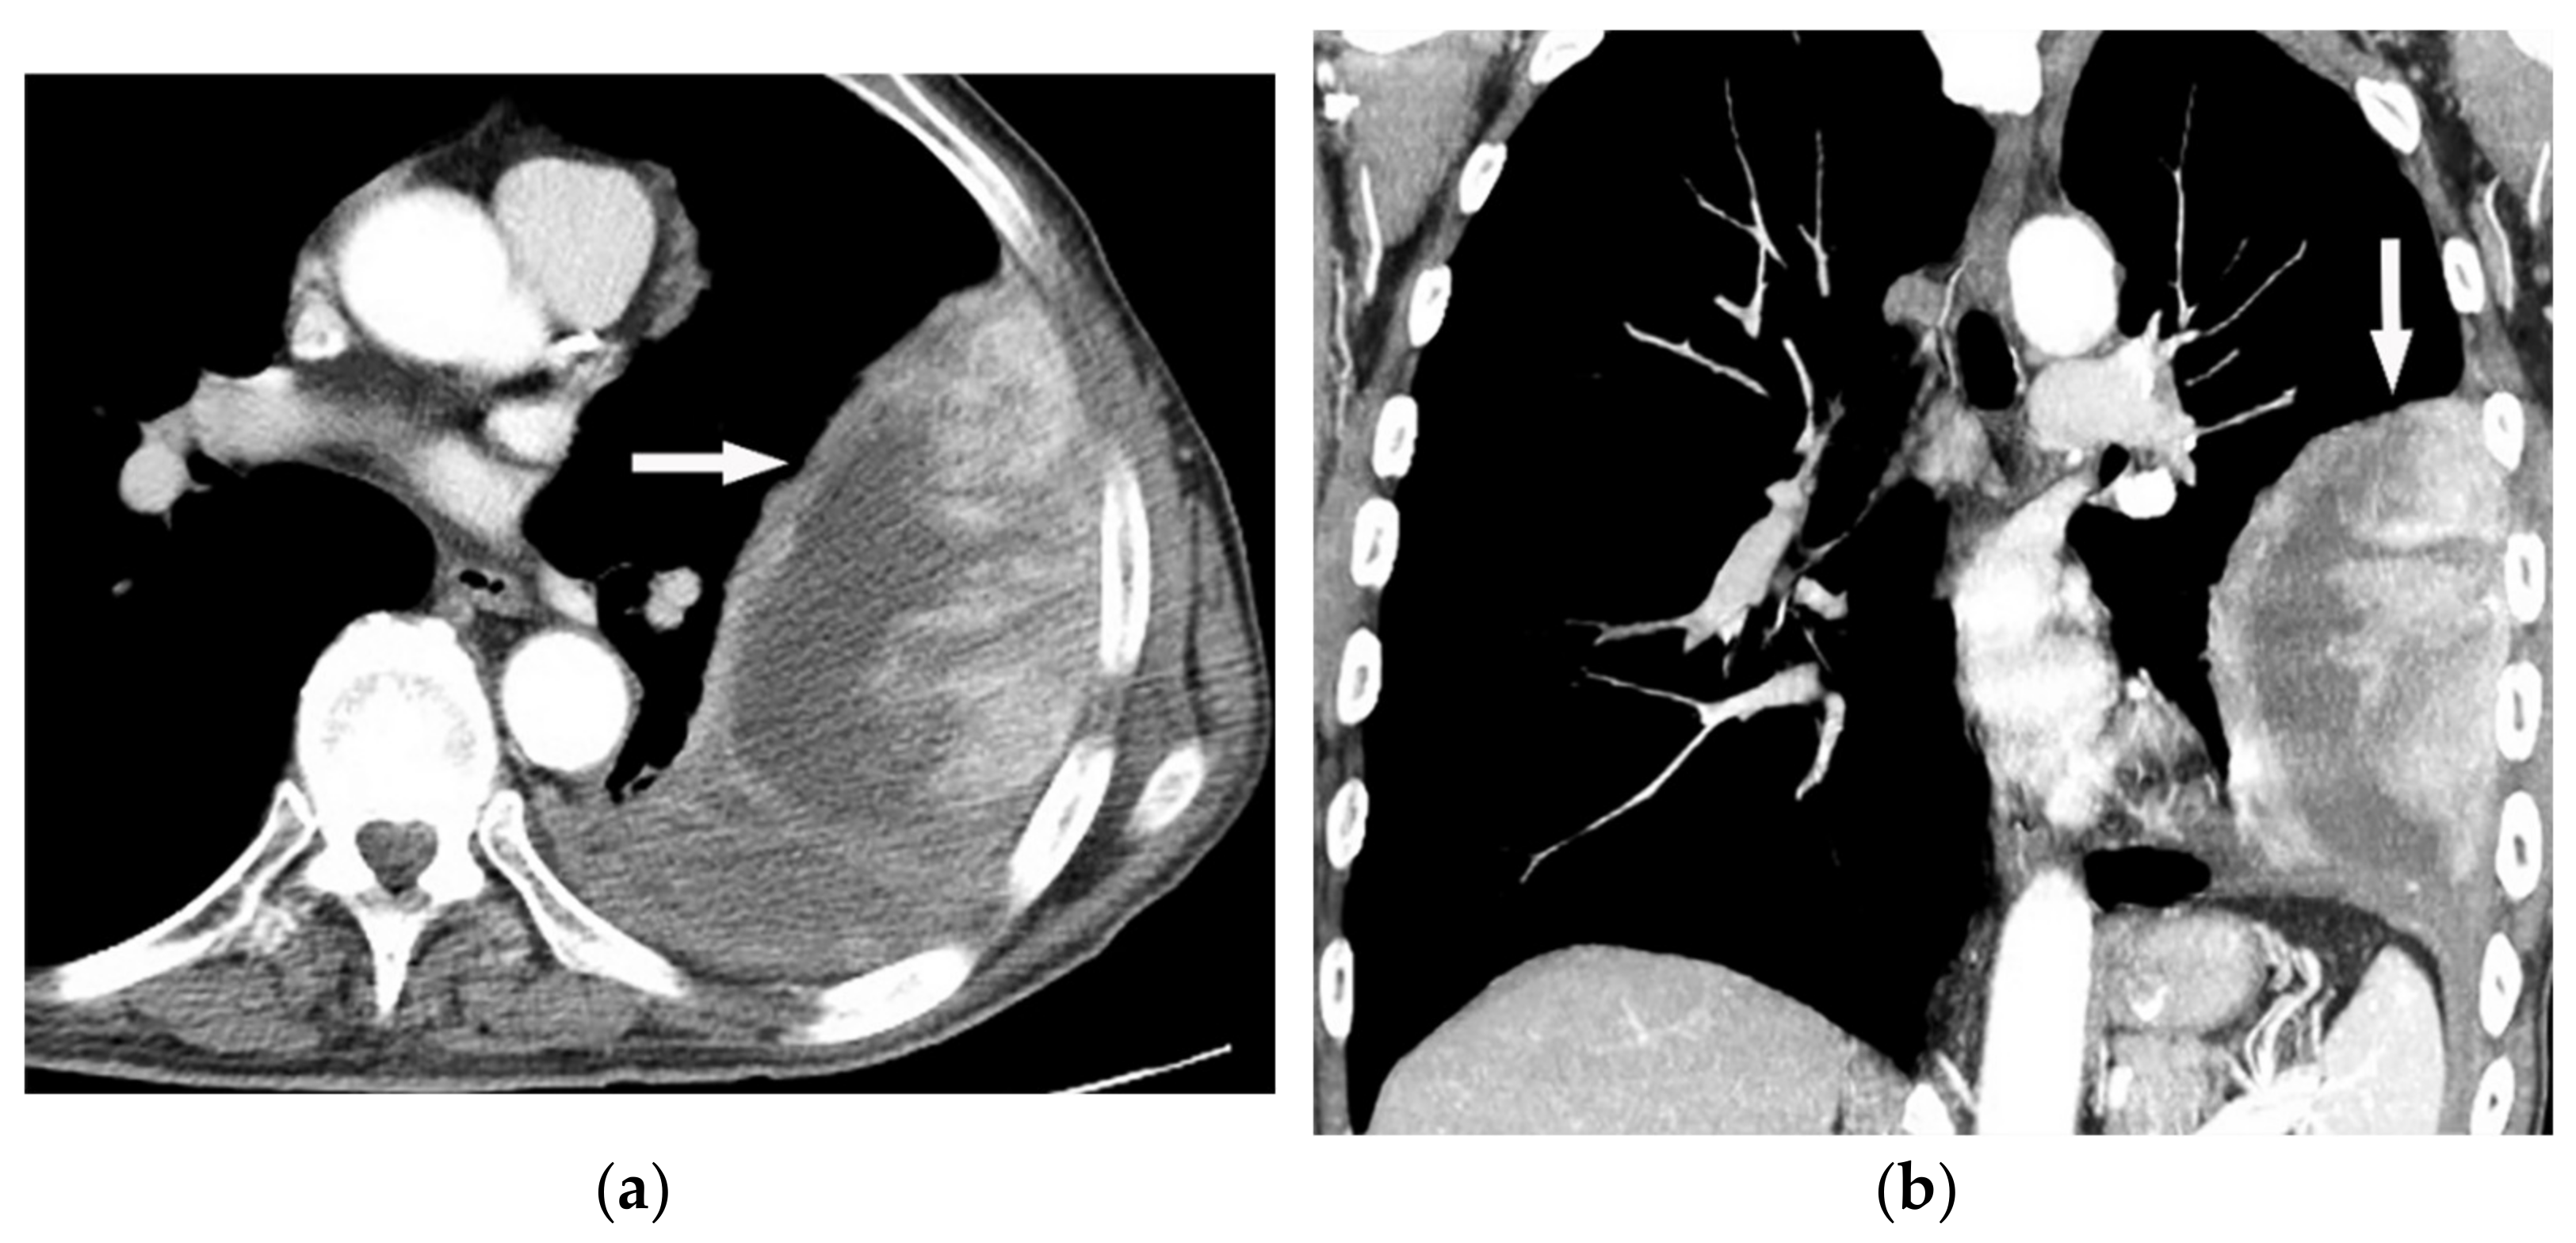

| Mesothelioma | Circumferential pleural thickening, bony or cartilaginous differentiation, unilateral pleural effusion, interlobular septal thickening, tumoral extension, thoracic and extrathoracic metastasis. | T1W: unilateral hyperintense pleural effusion, iso to slightly hyperintense pleural thickening T2W: moderately hyperintense T1WFS + C: typical enhancement is expected |